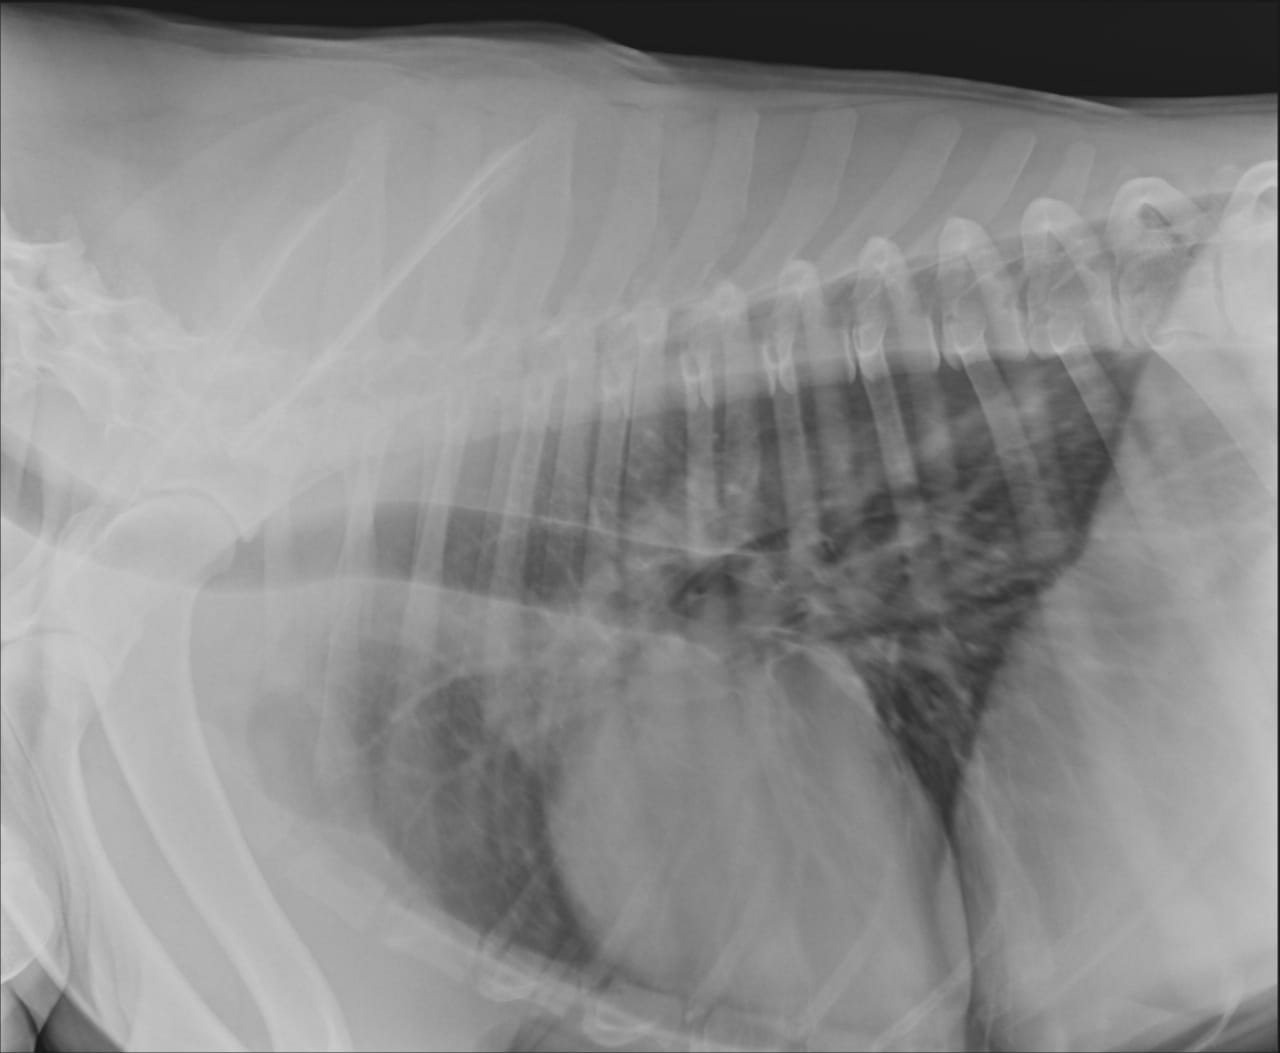

Анализы Арчи. Сердца и легких

Вложения

IMG-20220719-WA0100.jpg

IMG-20220719-WA0102.jpg

IMG-20220719-WA0104.jpg

IMG-20220719-WA0103.jpg

IMG-20220719-WA0105.jpg

Сегодня Арчуна Ирина возила на рентген легких и сдали анализ мочи. Результат анализа мочи готов будет завтра. Рентген легких выставляю.

Ирина, ждем твоего вердикта по рентгена и можно ли нам готовить Арчи к операции по глазам.

Антибиотика курс пропили.

Лучше чем было, но явно не норма:(